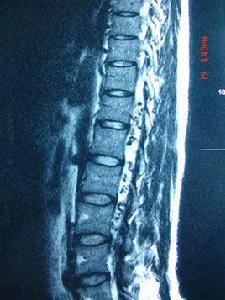

目前MRI 檢查是先天性脊髓腫瘤最為重要而常見的診斷檢查方法,病人有脊髓和神經根受壓的症狀及體徵,結合病人年輕,病史長,腰背部正中有皮膚異常,脊柱畸形等特點,都需要行MRI檢查來進一步的明確診斷。MRI基本上能夠做到定位、大部分定性診斷,同時了解其他畸形和脊髓拴系情況,因此對於診斷和治療該病起著重要作用。早發現、早期診斷關鍵在於我們廣大醫生提高對本病的認識積極的檢查處理。X 線和CT在診斷和治療中同樣起著重要作用。X 線平片可見明顯椎體畸形,椎管增寬,椎體後緣受壓凹陷,同時用做手術前椎體的定位。CT和重建檢查同樣是為了了解錐體骨性異常,同時也是為了手術前了解周圍的骨性異常。